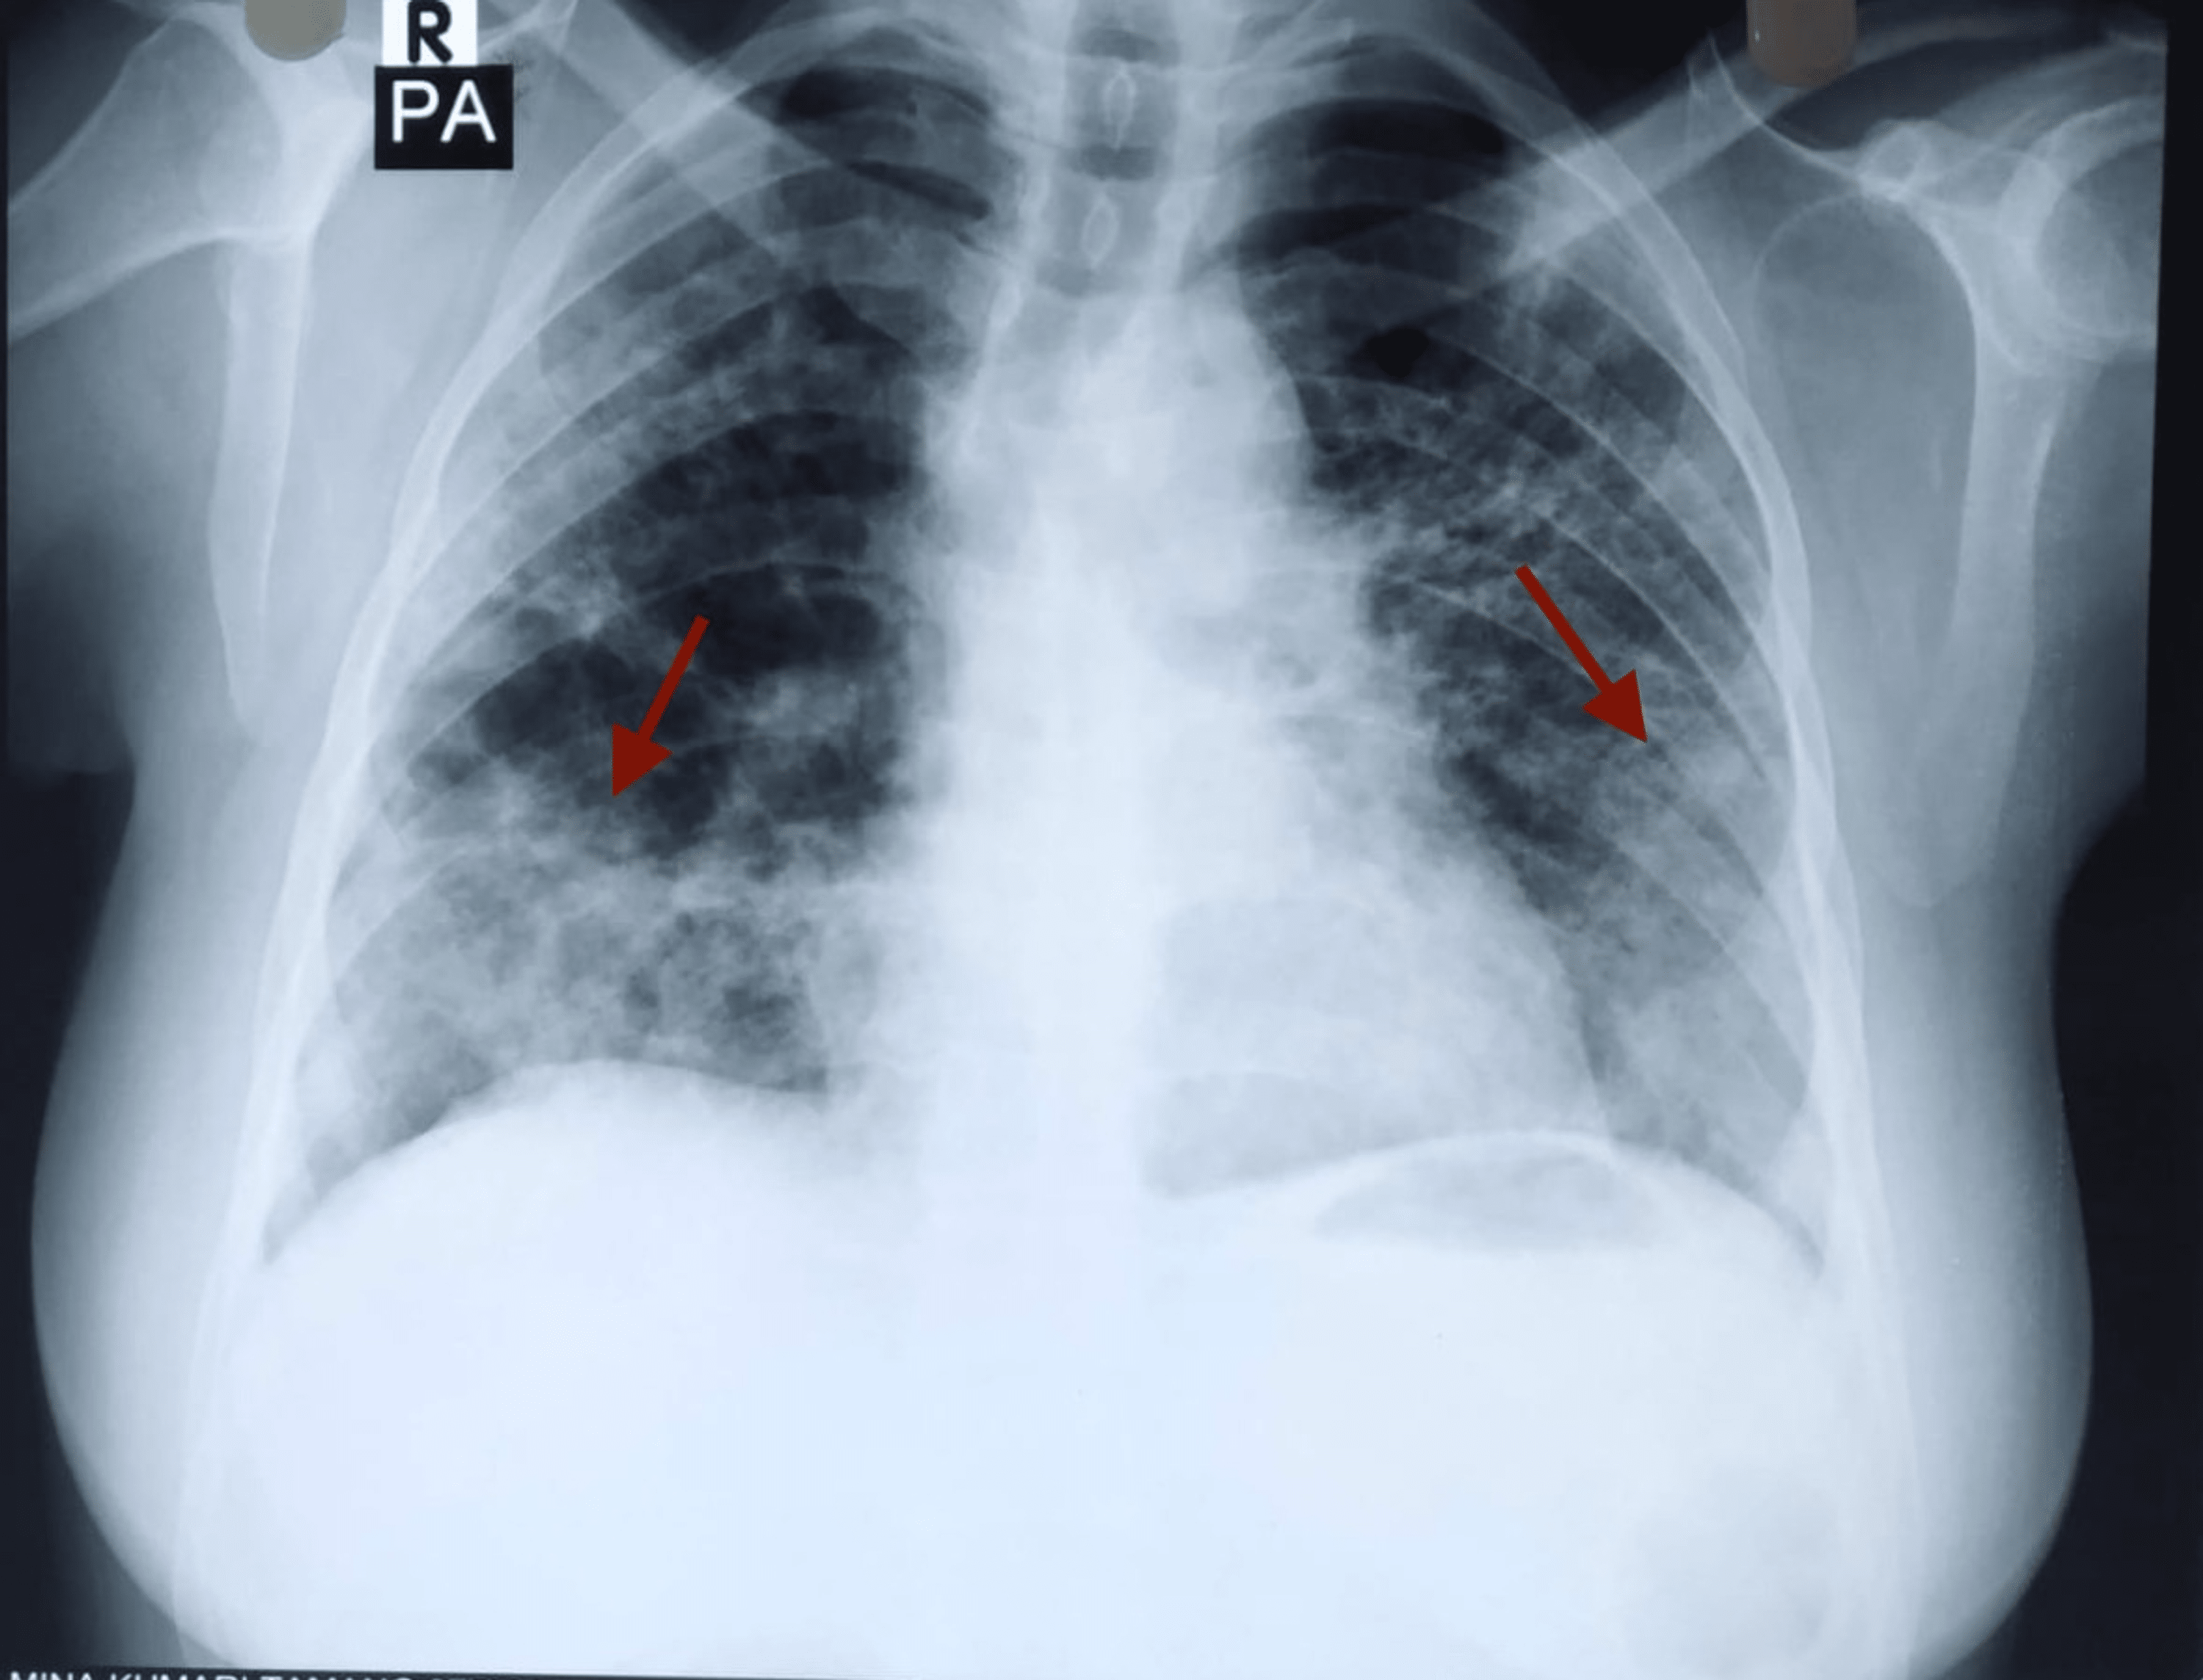

From www.researchgate.net

Investigation of ARDS chest Xray in studies of chronic pancreatitis D Does A Chest X-Ray Show Pancreatitis Ercp findings in chronic pancreatitis: Learn about the diagnosis, severity and complications of acute pancreatitis based on ct and mri findings. Used to look for free gas under the diaphragm (pneumoperitoneum) in patients who present with epigastric tenderness. Acute onset of persistent, severe epigastric pain (i.e. Acute pancreatitis is usually diagnosed in hospital, where you'll receive treatment and be monitored. Does A Chest X-Ray Show Pancreatitis.

From onlinelibrary.wiley.com

Thoracic complications of pancreatitis Kumar 2019 JGH Open Does A Chest X-Ray Show Pancreatitis In a patient with early chronic pancreatitis (a), mild dilatation of the main pancreatic duct (arrow) and side. Acute pancreatitis is a sudden and severe inflammation of the pancreas that causes abdominal pain, nausea, fever and jaundice. Learn about the diagnosis, severity and complications of acute pancreatitis based on ct and mri findings. Used to look for free gas under. Does A Chest X-Ray Show Pancreatitis.